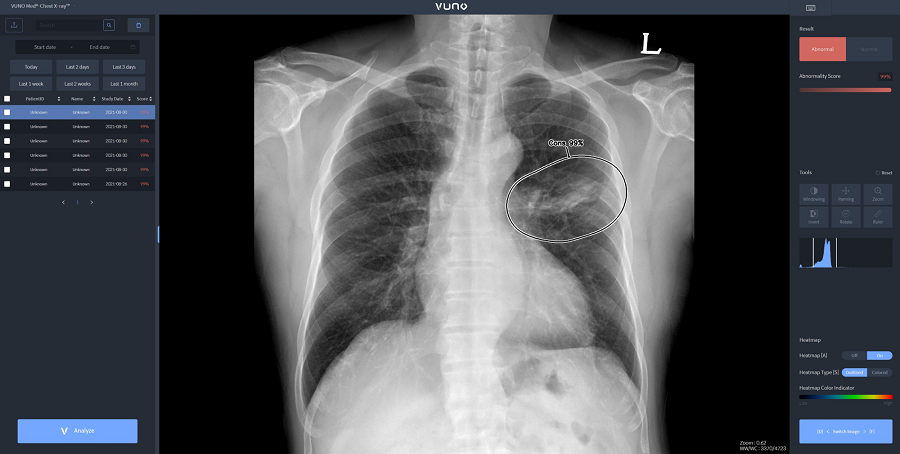

자이드 군 병원에 도입된 솔루션은 이동형 엑스레이 장비에 뷰노의 AI 기반 흉부 엑스레이 판독 보조 솔루션 뷰노메드 체스트 엑스레이™(VUNO Med®-Chest X-ray™)를 탑재한 패키지 제품이다. 별도의 차폐 시설 없이 다양한 상황에서도 쉽게 환자의 흉부 엑스레이 촬영을 할 수 있는 이동형 장비에 인공지능을 연동해 수 초 이내에 판독 결과를 확인할 수 있다.

한편, 뷰노메드 체스트 엑스레이™는 흉부 엑스레이 영상에서 결절, 경화, 간질성 음영, 흉수, 기흉 등 주요 이상소견을 높은 정확도로 탐지하는 인공지능 솔루션이다. 의료진에게 이상소견의 소견명과 위치를 제시해 결핵, 폐렴 등 주요 폐 질환 진단을 돕는다. 경량화된 모델로 개발돼 다양한 엑스레이 장비에 쉽게 연동할 수 있는 것이 특징이다.